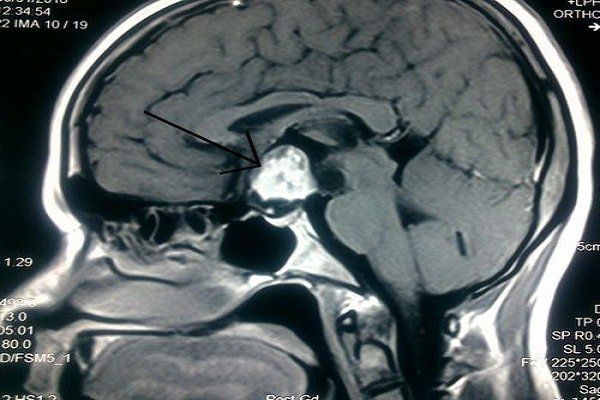

Để chẩn đoán và đánh giá khối u não, bác sĩ có thể chỉ định cho người bệnh thực hiện một trong các chẩn đoán kỹ thuật hình ảnh sau:

- Chụp MRI não: Chụp cộng hưởng từ (MRI) sử dụng từ trường mạnh, xung tần số vô tuyến và máy tính để tạo ra hình ảnh chi tiết của các cơ quan, mô mềm, xương và hầu hết tất cả các cấu trúc bên trong cơ thể. MRI cung cấp hình ảnh chi tiết nên có thể phát hiện các bất thường ở não như khối u và nhiễm trùng. MRI có độ nhạy cao để phát hiện khối u và đánh giá khu vực xung quanh nhằm xác định phạm vi ảnh hưởng của khối u.